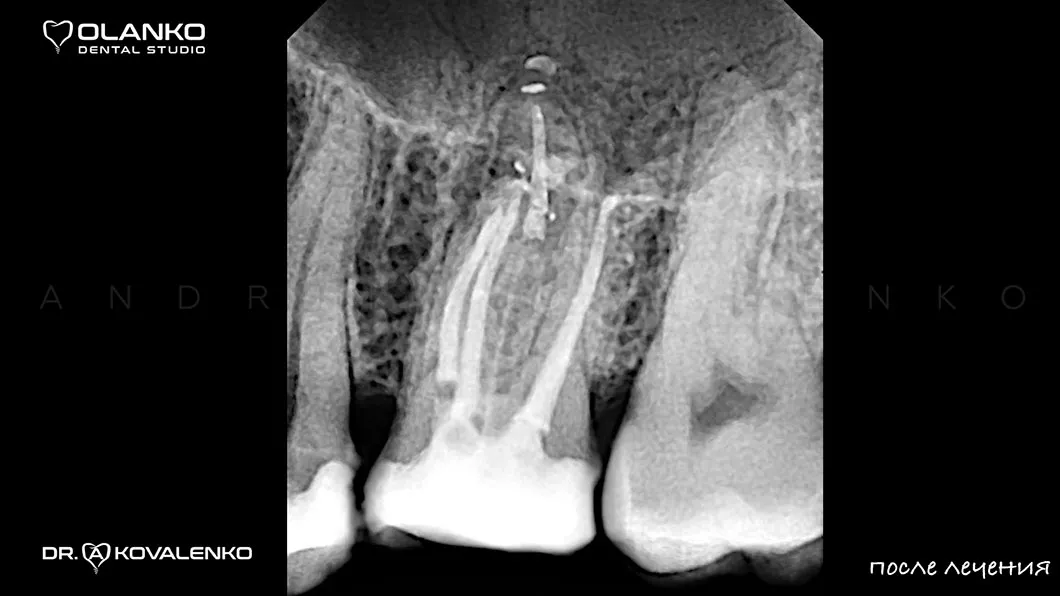

після

На сьогоднішній день, лікування зубів з використанням мікроскопу — це золотий стандарт світової стоматологічної практики. Складна система кореневих каналів має дуже малий діаметр та індивідуальну анатомію, тому лікар, який працює без збільшення, майже на дотик, не може якісно їх пролікувати.

Важливою перевагою Olanko dental studio (Оланко) м. Бровари є виконання всіх етапів лікування кореневих каналів тільки під контролем операційного дентального мікроскопу!

Для лікування простих клінічних випадків, як правило, потрібен всього один візит 1,5-2,5 години.

Складні випадки переліковування кореневих каналів, каналів зі складною анатомією, вимагають 2-3 візитів.